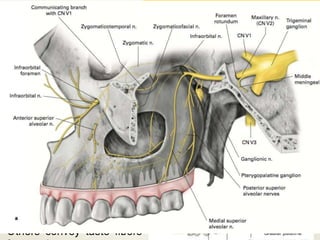

MAXILLARY NERVE

• Second division.

• It is purely sensory.

• The nerve leaves the middle cranial fossa through the foramen rotundum

to reach the Pterygopalatine fossa

Functions :

 Skin of face between lower eyelid and the mouth.

 From nasal cavity and sinuses

 Maxillary teeth and PDL tissues.

 Receives postganglionic

Parasympathetic fibers from

pterygopalatine ganglion

which

pass to the

LACRIMAL,NASAL and

PALATINE GLANDS.

Others convey taste fibers

Maxillary nerve gives off branches in four regions:

 Within the cranium : Middle Meningeal Nerve

 In the Pterygopalatine Fossa: Ganglionic branches

Zygomatic Nerves

Posterior Superior Alveolar Nerves

 In the Infraorbital Canal: Middle Superior Alveolar Nerves

Anterior Superior Alveolar Nerves

 On the face: Inferior Palpebral

Lateral/External Nasal

Superior Labial

Zygomatic Nerves :

I. Zygomaticotemporal nerve

II. Zygomaticofacial nerve

 Sensory innervation to skin over zygomatic region.

 Also conveys post ganglionic para symp fibers from pterygopalatine ganglion to

Lacrimal nerve and glands.

 It exits the fossa ,travels anteriorly, enters the orbit through infraorbital fissure and runs

along the lower part of lateral wall of the orbit.

 Then it enters the zygomatic bones and divides into two branches

Posterior Superior Alveolar Nerve:

 Descends from the main trunk of Maxillary nerve in the fossa.

 External branch provides sensory innervation to buccal gingiva in posterior maxilla.

 Other branch enters the maxilla through the posteriorolateral wall of sinus, and provides

sensory innervation to mucous membrane of sinus,alveoli,PDL and pulpal tissues of

maxillary molars.

 Mesiobuccal root of first molar is

not innervated by PSAN in 25% of

individuals.

Infraorbital Nerve:

 Middle Superior Alveolar Nerve

 Anterior Superior Alveolar Nerve

 It passes forwards along the floor of the orbit, sinks into the groove , then enters the canal

and emerges on the face through IO foramen.

 MSAN-premolars ,MB root of first molar,PDL tissues,buccal soft tissue.

 ASAN- C.I, L.I , Canines, PDL tissues, buccal bone and gingiva of these teeth.

MANDIBULAR NERVE

• Third division and the largest branch.

• Mixed nerve.

• Nerve of first branchial arch.